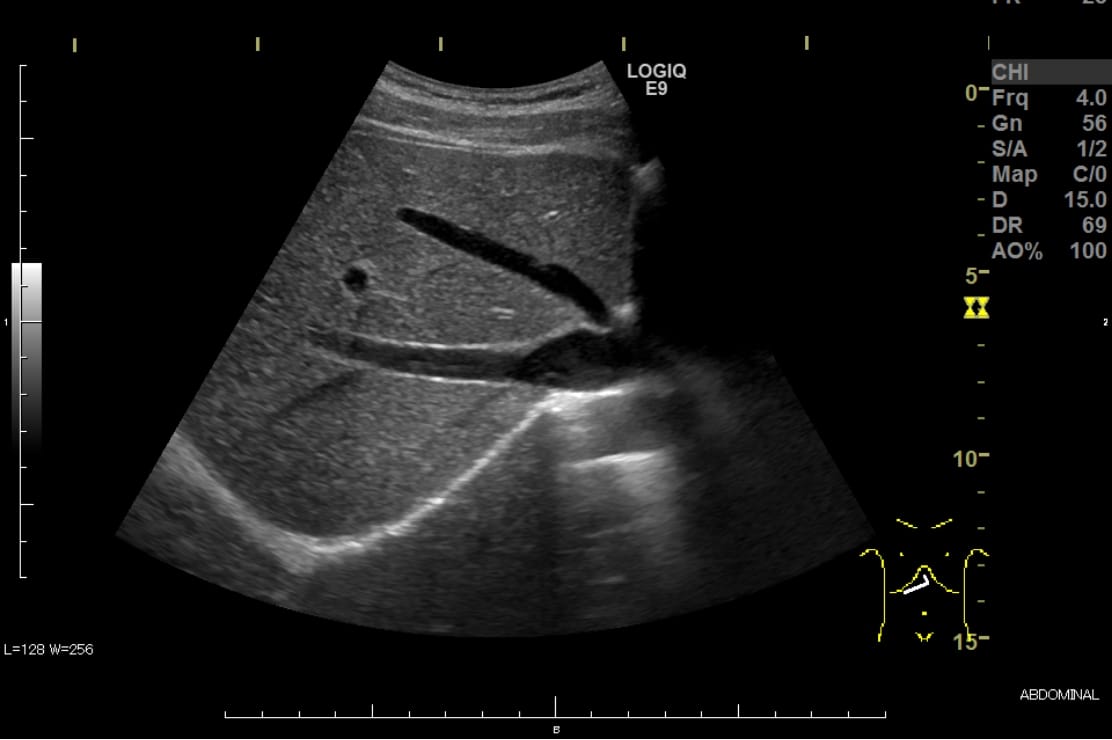

腹部超音波検査

(腹部エコー検査)

肝臓・胆嚢・膵臓・腎臓・脾臓・大動脈・膀胱・前立腺・子宮・卵巣・消化管などの状態を調べます。

各臓器の腫瘍や炎症、結石や脂肪肝など異常の有無が確認できます。

ベッドの仰向けに寝ていただき、お腹にゼリーを塗り観察します。検査時間は観察内容にもよりますが10~20分程度です。

検査中は息を吸ったり止めたりの呼吸調整や、必要に応じて体位変換(側臥位・座位など)を行います。体位変換が困難な場合はお知らせください。

検査目的によって絶食や水分制限が必要になります。

膀胱や骨盤内臓器を見る場合は尿を貯めた状態で検査をします。

事前に指示された内容に従ってください。

超音波診断装置(腹部・表在用)

肝臓の超音波画像